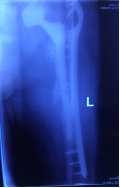

病例3 患者何某,男性,78歲,左髖關(guān)節(jié)置換術(shù)后6年,出現(xiàn)疼痛、活動(dòng)困難1年,診斷為“左髖關(guān)節(jié)置換術(shù)后假體松動(dòng)”,患者身體瘦弱,既往有高血壓病、冠心病、心肌梗死等病史,進(jìn)行髖關(guān)節(jié)翻修手術(shù),存在一定的風(fēng)險(xiǎn),必須較好的控制手術(shù)節(jié)奏,同時(shí)確保手術(shù)順利和病人生命安全,專家團(tuán)隊(duì)匯集麻醉科、內(nèi)科、ICU團(tuán)隊(duì),進(jìn)行了詳盡的手術(shù)中、手術(shù)后的計(jì)劃和預(yù)案,手術(shù)得以順利實(shí)施,術(shù)后經(jīng)過骨科、內(nèi)科、ICU團(tuán)隊(duì)的配合,患者得到良好的恢復(fù)。

術(shù)前X線片

術(shù)后X線片